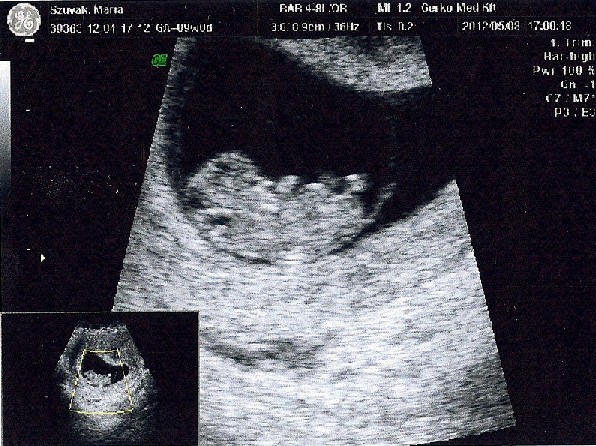

Lombikbaba, ezek a fotók... jó nektek...!